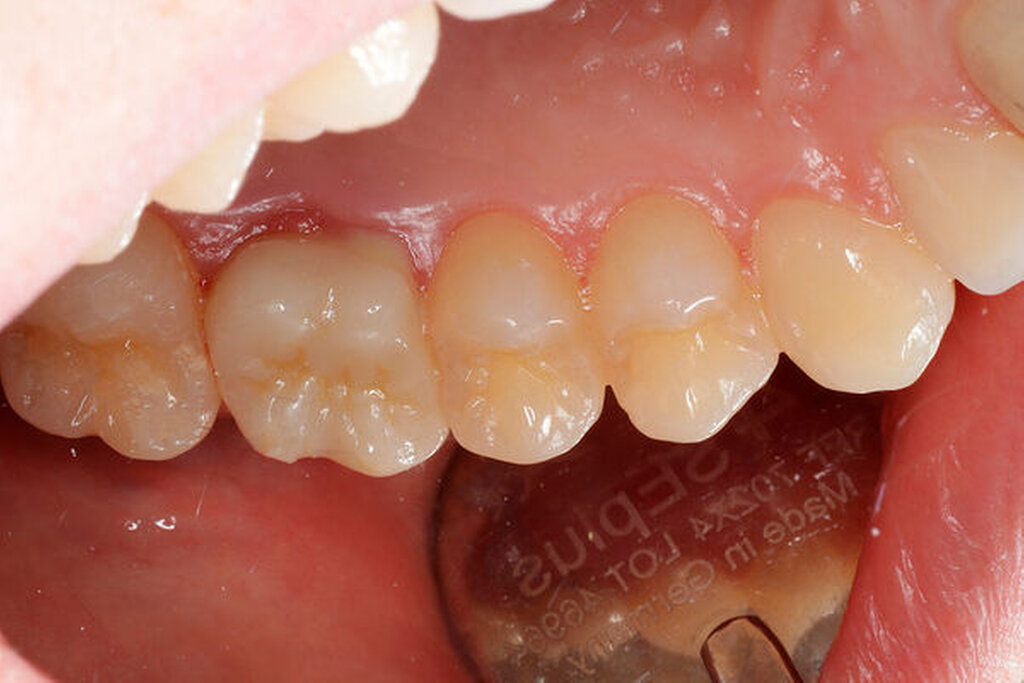

Eine 22-jährige Patientin stellte sich erstmals im Sommer 2017 mit rezidivierenden Beschwerden an dem alio loco endodontisch behandelten Zahn 16 vor. Nach ausgiebiger Aufklärung über die Therapieoptionen bei Verdacht auf einen unbehandelten mb2 erfolgte die Revisionsbehandlung des Zahnes mit der Empfehlung, diesen aufgrund des großen Substanzdefekts zur Stabilisierung zeitnah zu überkronen. Bevor die Überkronung durchgeführt werden konnte, frakturierte der palatinale Höcker. Bei der Inspektion unter dem Operationsmikroskop war sichtbar, dass sich die Fraktur als Längsfraktur in die palatinale Wurzel fortsetzte. Mit der Patientin wurden nun die Optionen der Teilamputation der frakturierten Wurzel oder alternativ der Extraktion des Zahnes besprochen. Sie entschied sich für den Erhaltungsversuch.

Darauf erfolgte die Amputation der palatinalen Wurzel mit anschließender Versorgung durch eine vollkeramische Krone. Die Situation ist nach inzwischen drei Jahren weiterhin stabil, die Patientin kommt mit der Versorgung gut zurecht, lediglich palatinal finden sich leicht erhöhte Sondierungstiefen.